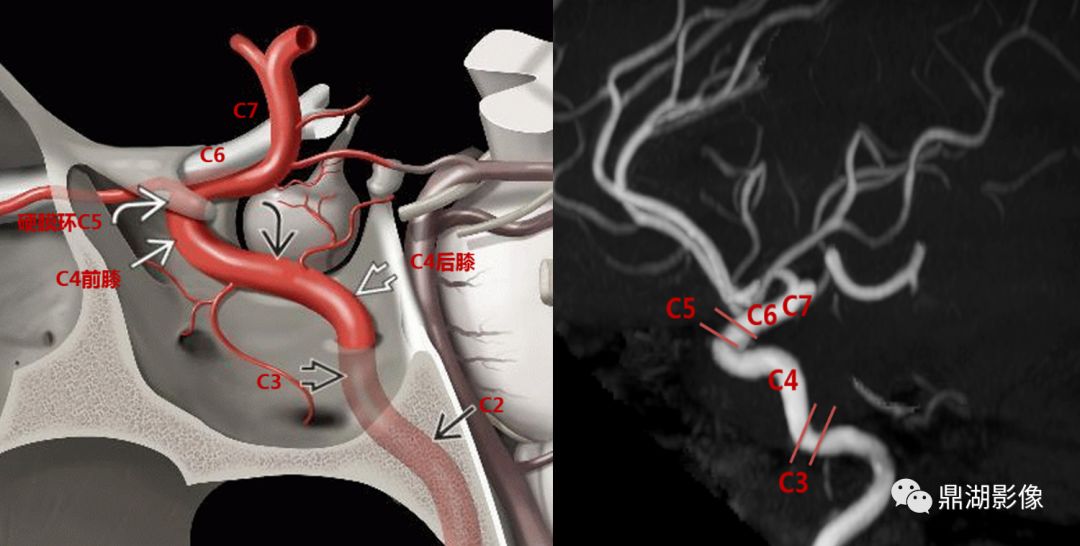

【超实用】今天学会颈内动脉cta分段

颈内动脉c6段在侧位脑血管造影显示最清楚, 在与c5段(床突段)交界处远